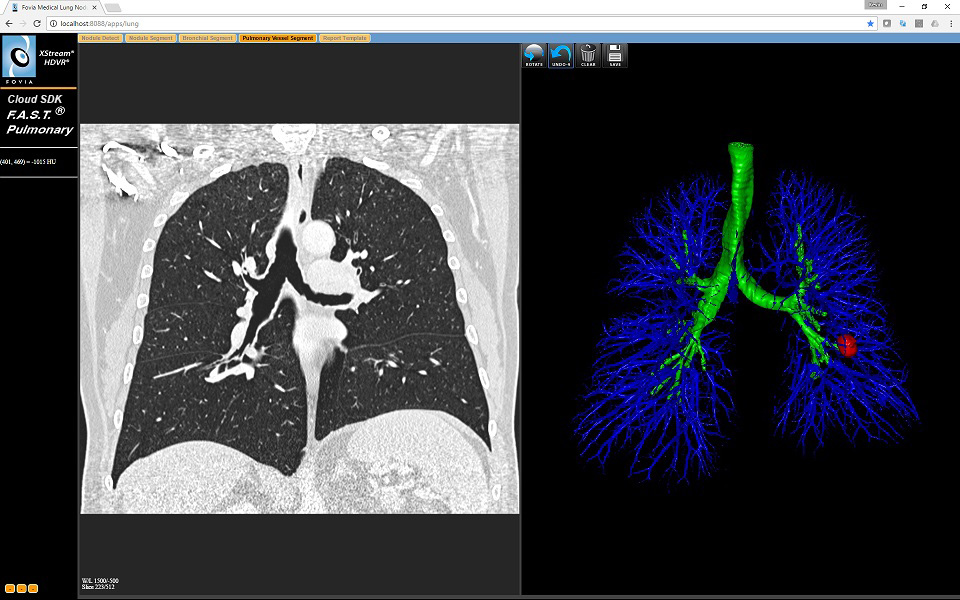

The Pulmonary Vessel Segment Tab of the application consistsUpdated code comments and cleaned up dead code in Cardiac apps. of 2

viewports

Segmenting the pulmonary vessels is a challenge. Using a simple grow

with a HU range the segmentation leaks into the heart tissue since the

density of the blood in the pulmanry vessel tree is exactly the same as

the blood in the heart. So we created a workflow here to get just the

pulmonary vessels. First the lung fields are segmented using simple HU

Range Interactive Segmentation. Next a series of dilate and erode

operations are used to find the blood density ranges left inside the

lung fields and finally remove the tissue around the lung fields where

it touches the chest wall.

Left – Sagittal image for selecting start points to segment the lung fields. Just like the prior two segmentations.

Right – 3D View with resulting segmentation. Toggle the

first "on viewport" button to select pulmonary vessels from the lung

fields segmented in the first step (after selecting that mode, click on

the lung field to process). After this there are 4 new on viewport

buttons. These allow you adjust the number of "open" and "close"

operations that are performed (the default setting perform well on most

cases, but for some patients you need to adjust these) click on the 5th

button to finish the pulmonary segmentation and return to normal

viewport control.

The Pulmonary Vessel Segment Tab of the application consistsUpdated code comments and cleaned up dead code in Cardiac apps. of 2 viewports

Segmenting the pulmonary vessels is a challenge. Using a simple grow with a HU range the segmentation leaks into the heart tissue since the density of the blood in the pulmanry vessel tree is exactly the same as the blood in the heart. So we created a workflow here to get just the pulmonary vessels. First the lung fields are segmented using simple HU Range Interactive Segmentation. Next a series of dilate and erode operations are used to find the blood density ranges left inside the lung fields and finally remove the tissue around the lung fields where it touches the chest wall.